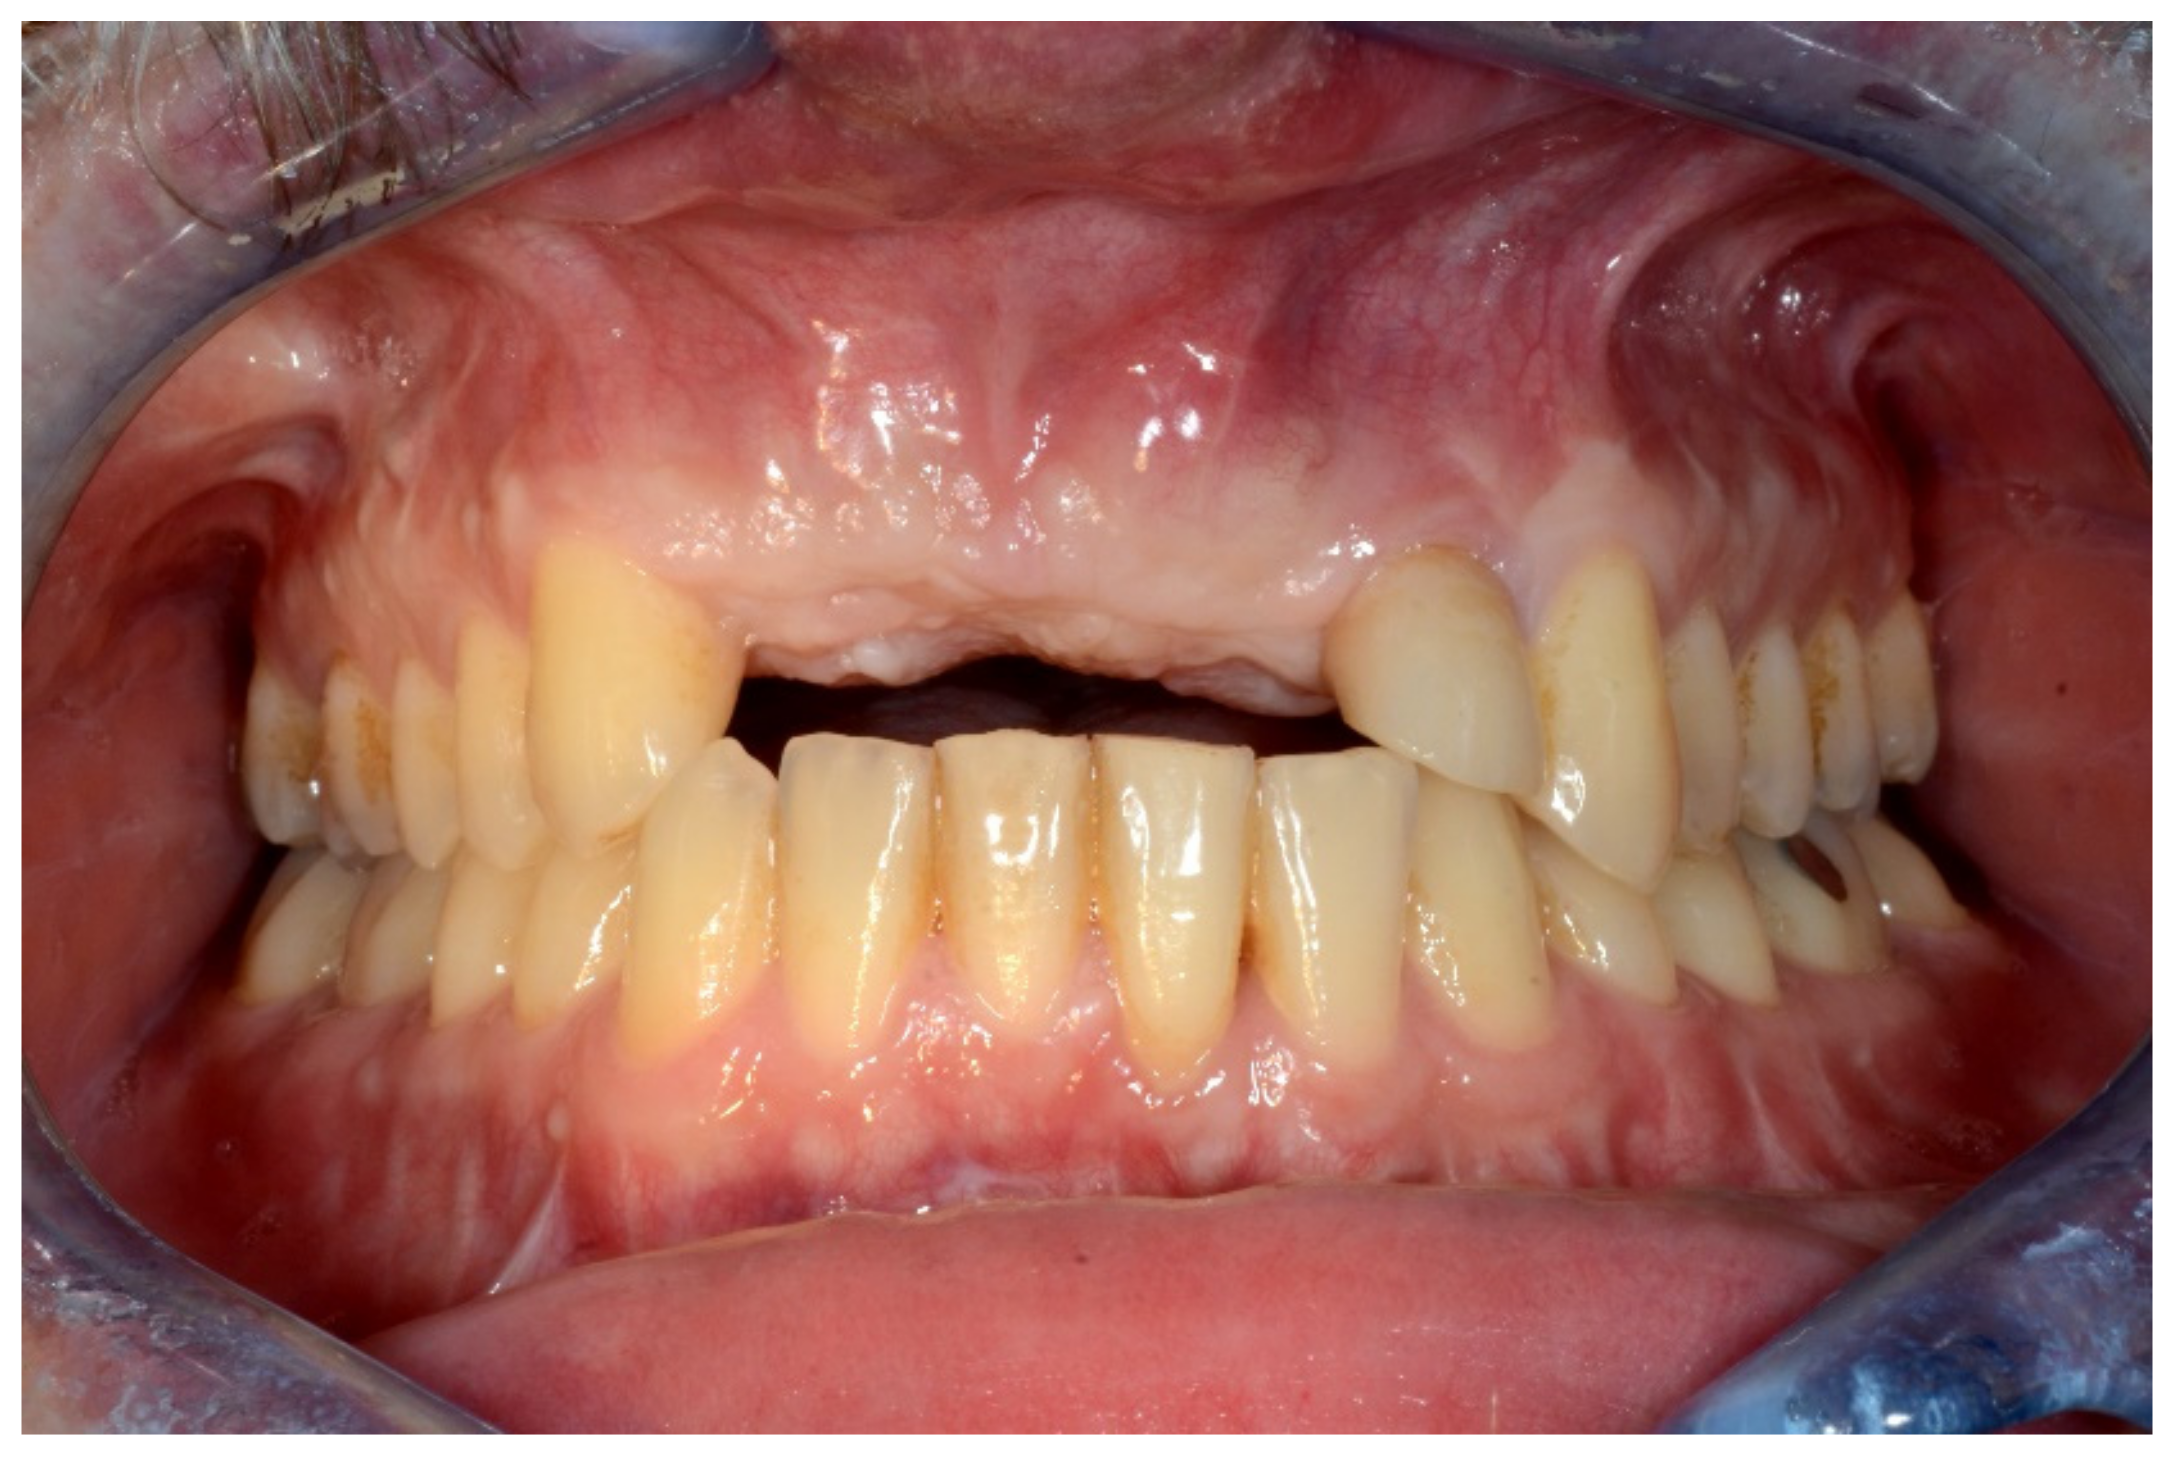

6.2.1. Severe Partial Edentulous Maxilla and Complete Edentulous Mandible (Maxillary and Mandibular Screw-Retained Implant-Supported Bridges)

6.2.2. Preoperative Documentation